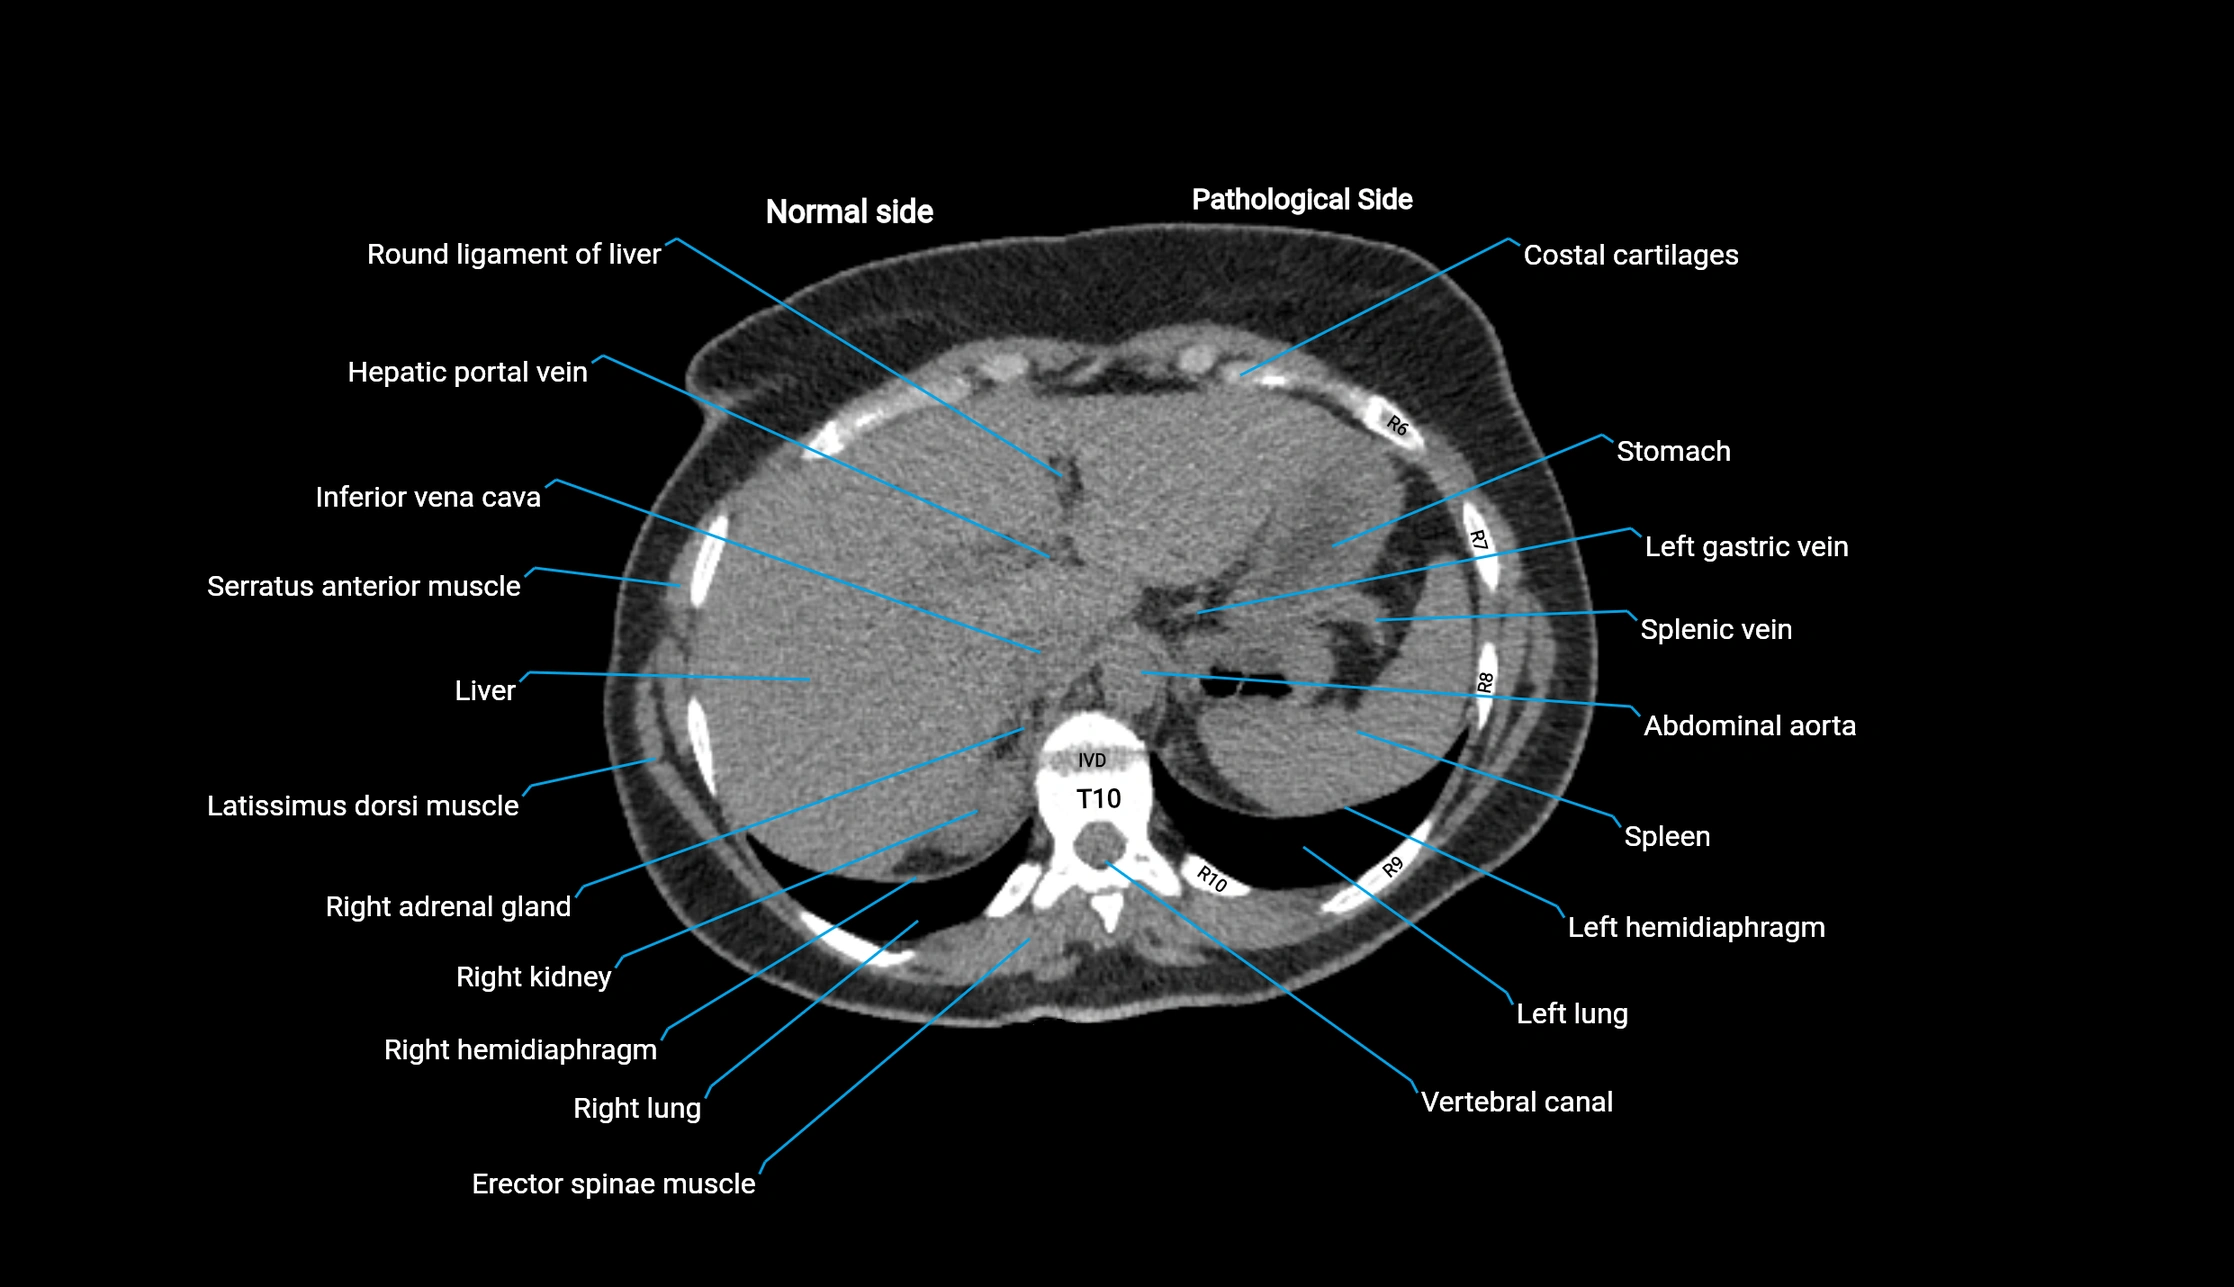

Post-Contrast CT (Contrast-Enhanced CT):

• Portal venous phase:

• Anterior right portal branch enhances intensely and homogeneously

• Clearly separates from posterior branch

• Branching pattern to segments V and VIII sharply defined

• Arterial phase:

• Slight enhancement but less conspicuous than in portal phase

• Coronal and sagittal reconstructions:

• Optimal visualization of segmental bifurcation

• Used for preoperative liver mapping

• CT liver segmentation:

• RAPV acts as the principal boundary landmark for dividing anterior vs. posterior right hepatic segments